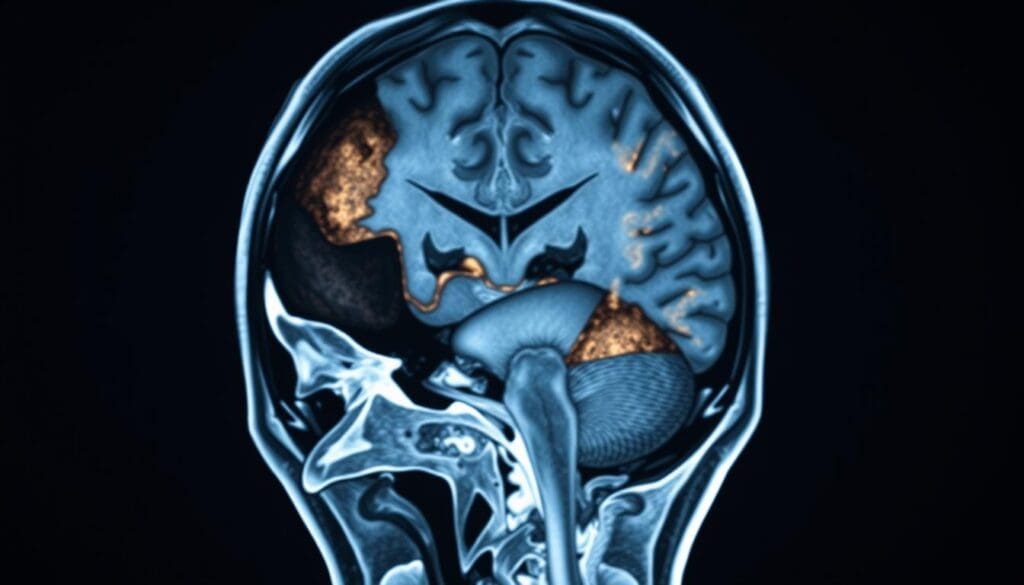

Brain Hemorrhage Complications in Coma Recovery

Brain hemorrhage is a serious issue that can happen after head trauma. It makes recovery from coma harder. When someone gets head trauma, they are more likely to get a brain hemorrhage. This makes their future look uncertain.

Types of Intracranial Bleeding

Intracranial bleeding, or hemorrhage, can happen in different ways. Each type affects coma recovery differently. Knowing about these types helps doctors choose the right treatment.

Subdural vs. Epidural Hematomas

Subdural and epidural hematomas are two kinds of bleeding. Subdural hematomas happen under the dura mater, a brain protector. Epidural hematomas happen between the dura mater and the skull. Both can raise pressure inside the skull, making coma recovery harder.

Intracerebral hemorrhage is bleeding right into the brain. It can damage brain cells and structures. This affects brain functions and makes coma recovery more challenging.

How Bleeding Location and Extent Affect Prognosis

The place and size of bleeding are key in coma patient outcomes. How severe the bleeding is and where it is in the brain matters a lot. It affects how well a patient can recover.

Patients with bleeding in important brain areas might have a tougher time. Those with bleeding in less critical spots might have a better chance. Also, bigger bleeds usually mean a worse outcome.